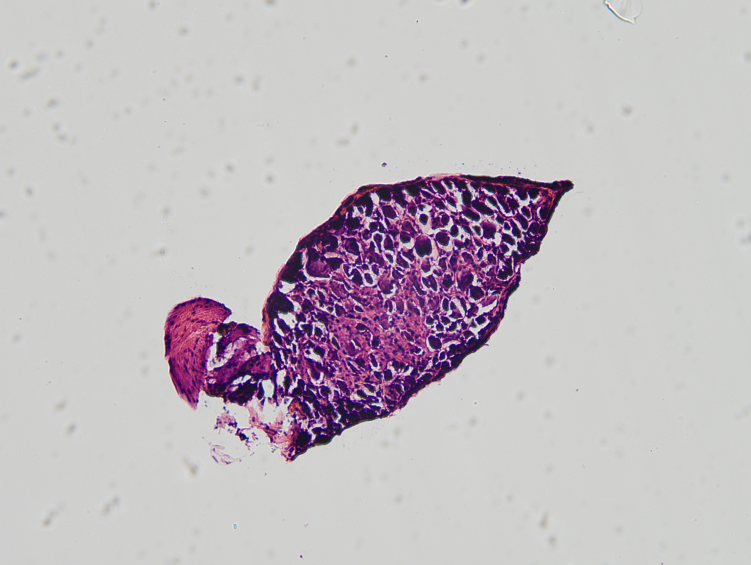

5. 暴露L4-6背根神经节;

6. 坐骨神经和L4-6背根神经节;

7. 背根神经节HE染色。